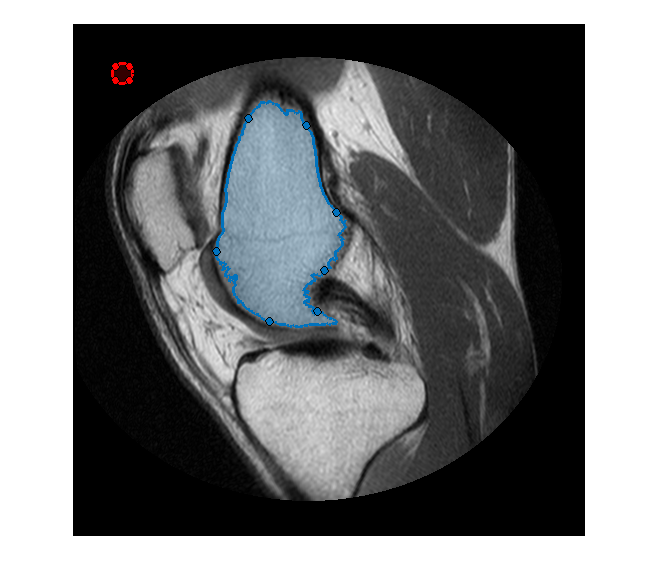

Сегментируйте изображение MRI и выберите две самых больших области рисунка маски.

segmentedLabels = imsegkmeans(im,3); boneMask = segmentedLabels==2; boneMask = bwareafilt(boneMask, 1);

Получите координаты контуров двух сегментированных областей.

blocations = bwboundaries(boneMask,'noholes');

Преобразуйте местоположения, возвращенные bwboundaries в x, y порядок.

pos = blocations{1};

pos = fliplr(pos);

Создайте ROI от руки в сегментированной маске.

hf = drawfreehand('Position', pos);